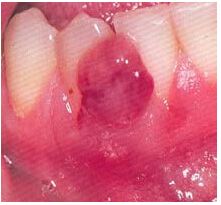

28. 男性 33 歲,一周前進行 38 根管治療,回診發現 38 周圍黏膜有白色無痛病灶(如下圖)請問引發病灶原因為何?(A) Chemical --- endodontic treatment (次氯酸鈉沖洗液) (B) Ulcer (C) Leukoplakia (D) Thermal bure